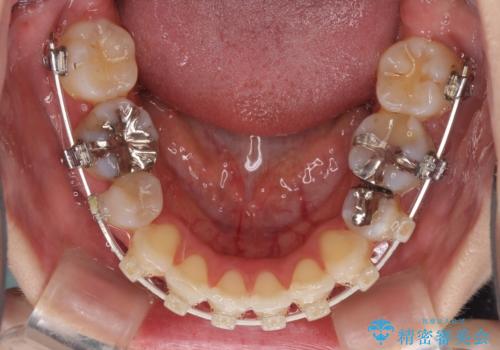

目立たないハーフリンガル矯正 抜歯矯正で口元を改善

- ハーフリンガル

目立たない装置を希望されたので、上顎が裏側装置のハーフリンガルを選択し、上下左右の小臼歯(計4歯)を抜歯して矯正治療を行うこととしました。

治療期間の目安は3年~3年半でしたが、咬み合わせにより上顎のスペースがなかかな閉じきらず、治療期間が長期化してしまいました。

期間はかかったものの、口元の張り出し感や歯のデコボコが解消され、患者様には大変満足していただけました。